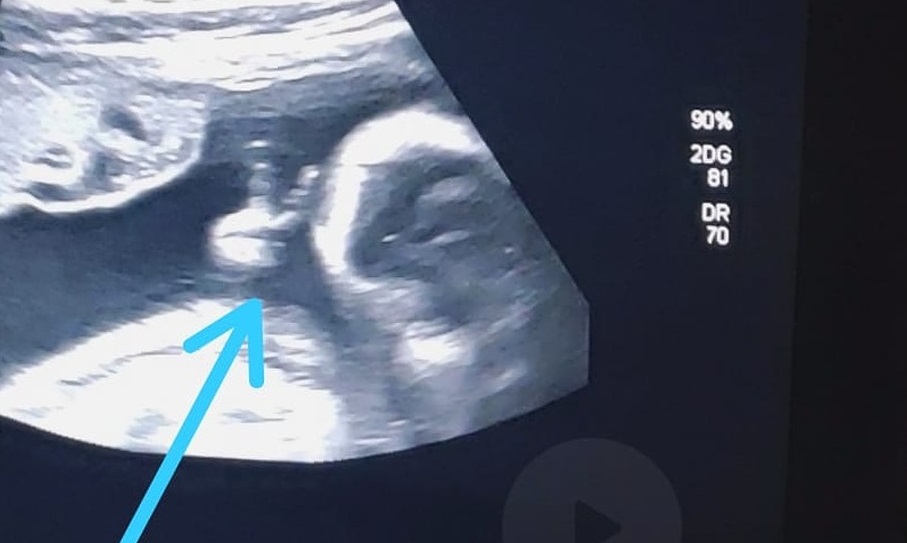

Bebê fez ‘sinal de vitória’ durante ultrassom — Foto: Arquivo Pessoal/Felipe Moreira dos Santos

Felipe Moreira dos Santos, de 32 anos, se surpreendeu durante exame de ultrassonografia de sexto mês do primeiro filho. Nas imagens, o bebê aparece fazendo um ‘V de vitória’ com a mãozinha, dentro do útero. O morador do Guarujá, no litoral de São Paulo, que enfrenta um raro câncer no baço, encarou a situação como um ‘sinal divino’. As informações são do portal G1.

Para o rapaz, poder ver o ultrassom já é bem emocionante, por observar como o bebê está e ouvir seu coraçãozinho. Mas, desta vez, ele se deparou com a surpresa de ver o filho Davi fazendo um sinal de ‘V’ com uma das mãozinhas. “Até a médica falou: ‘olha, ele fez o sinalzinho de vitória com a mão’. Eu fiquei sem acreditar”, afirma. Ele encara a situação como um sinal divino de que vai conseguir superar o tratamento e vencer a doença”, finalizou, em entrevista ao G1.